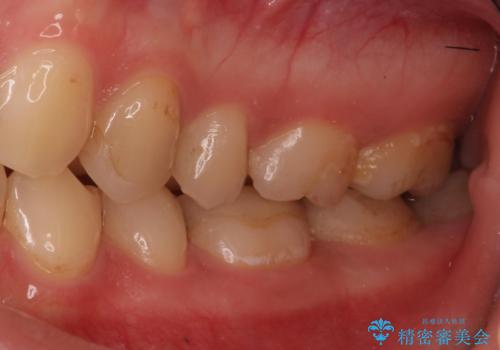

精度の低い詰め物のやり替え

- セラミックのつめものの精度が低かったためやり直しを行いました。

歯の高さがなく、またセラミックアンレーは割れるリスクが高いため、セラミックのアンレーとはせず、クラウンとし、さらに割れにくいようにヴェレッツァクラウンとしました。